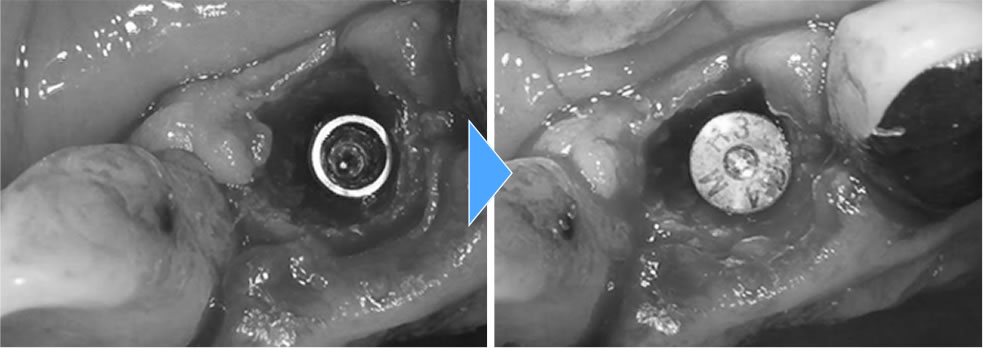

割れた前歯を抜歯即時インプラントで治療した症例

年齢

40代

性別

女性

症例を見る